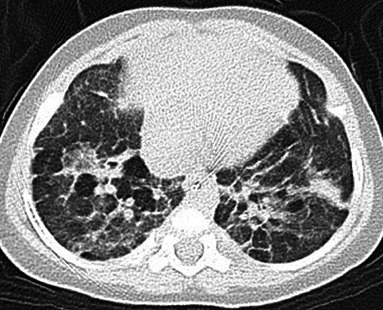

Home high-flow nasal cannula (HFNC) use in the neonatal field has become prevalent as a noninvasive respiratory support, but its application in home care remains rare. We report two cases in which a home HFNC was effective in managing extremely low-birth-weight infants with severe bronchopulmonary dysplasia (BPD). Case 1 was a male infant born at 22 weeks' gestation weighing 435 g. Case 2 was a female infant born at 23 weeks' gestation weighing 450 g. Both patients had mothers with chronic placental abruption or chorioamnionitis. They transitioned from invasive mechanical ventilation to nasal CPAP (nCPAP) at 45 days (case 1) and 50 days (case 2) old. Subsequently, at 324 days (case 1) and 90 days (case 2) old, they transitioned to a HFNC, demonstrating stable oxygenation and ventilation, but faced difficulty in removal. Considering the drawbacks of prolonged hospitalization, the patients were discharged using a home HFNC at 404 days (case 1) and 391 days (case 2) old. For case 1, the HFNC was set at 4 L/min of room air and 2 L/min of oxygen, whereas for case 2, it was set at 5 L/min of room air and 1 L/min of oxygen. These settings maintained an SpO2 above 90% and a pCO2 below 60 mmHg. An HFNC offers advantages over nCPAP owing to its lower invasiveness and reduced discomfort for long-term use. However, reports on the use of a home HFNC for BPD are scarce. In recent years, while premature infant mortality has decreased worldwide, the incidence of BPD has risen, necessitating preparedness for prolonged ventilation in preterm infants. Home ventilators represent a strategy to prevent extended hospitalization, and based on our cases, home HFNC for BPD appears safe and effective, making it potentially useful for managing preterm infants requiring prolonged respiratory support in the future.